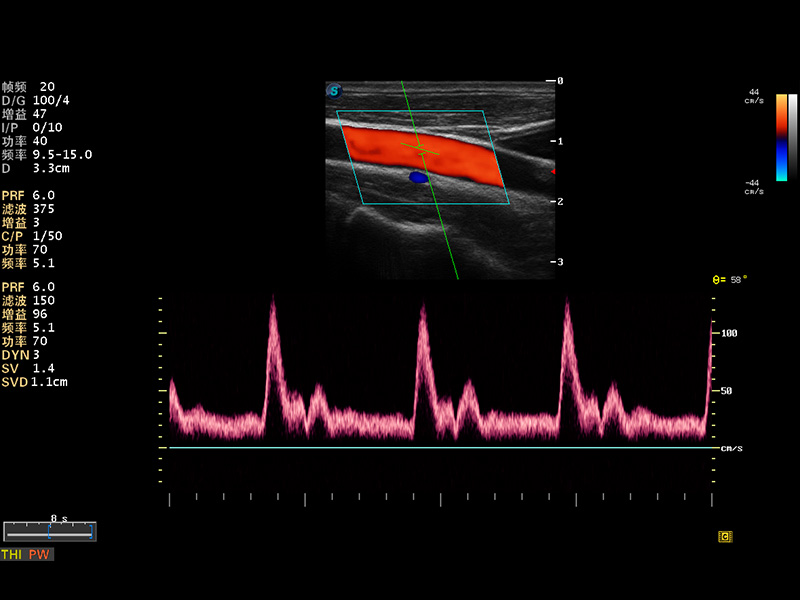

S8 EXP便携式彩色多普勒超声诊断仪是百老汇电子游戏官网研发的高端全身应用型便携彩超。高通道的VIS平台融合可视化(Visual)、智能化(Intelligent)和人性化(Smart)的特点,配以百老汇电子游戏官网自主研发生产的探头大家族,使您能够快速、准确的获得病人信息,提高工作效率的同时减轻疲劳。

多波束形成器

μ-Scan微米成像

谐波成像